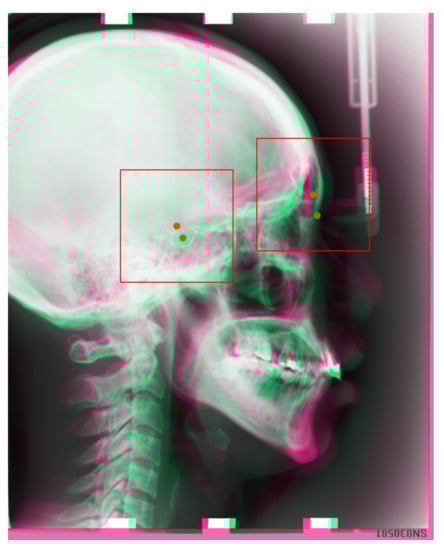

After registration, we copy the landmark locations of the reference images (training images) to moving images (test images). We consider the landmark location of a reference image as the center of the ROI patch, extract a 512 × 512 resolution patch image on the moving image, and then resize it to a 256 × 256 resolution patch for the test. The extracted images will be treated as input to our trained convolutional neural network (CNN); thus, we can detect the corresponding landmark in the patch image. The registration results are presented in Figure 5.

Figure 5. In the image, we take the reference image’s landmarks(Training images) as center of the patch image, then we draw a bounding box (ROI) in the test image, as the input to our corresponding trained models. Red dots are the reference images’ landmarks, green dots are test image’s landmarks, which are the landmarks we aim to detect.